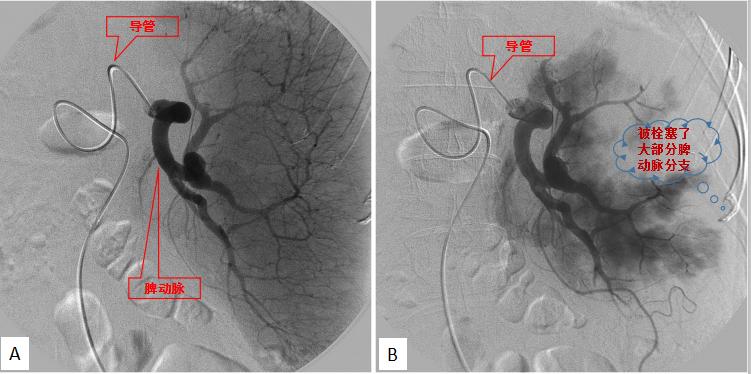

脾亢患者行部分性脾动脉栓塞术 A.介入前;B.介入后